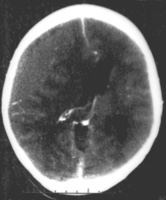

Subdural hematoma as marked by the arrow with significant midline shift

It is important that a person receive medical assessment, including a complete neurological examination, after any head trauma. A CT scan or MRI scan will usually detect significant subdural hematomas.

Subdural hematomas occur most often around the tops and sides of the frontal and parietal lobes.[3][4] They also occur in the posterior cranial fossa, and near the falx cerebri and tentorium cerebelli.[3] Unlike epidural hematomas, which cannot expand past the sutures of the skull, subdural hematomas can expand along the inside of the skull, creating a concave shape that follows the curve of the brain, stopping only at dural reflections like the tentorium cerebelli and falx cerebri.

On a CT scan, subdural hematomas are classically crescent-shaped, with a concave surface away from the skull. However, they can have a convex appearance, especially in the early stages of bleeding. This may cause difficulty in distinguishing between subdural and epidural hemorrhages. A more reliable indicator of subdural hemorrhage is its involvement of a larger portion of the cerebral hemisphere. Subdural blood can also be seen as a layering density along the tentorium cerebelli. This can be a chronic, stable process, since the feeding system is low-pressure. In such cases, subtle signs of bleeding—such as effacement of sulci or medial displacement of the junction between gray matter and white matter—may be apparent.

Fresh subdural bleeding is hyperdense, but becomes more hypodense over time due to dissolution of cellular elements. After 3–14 days, the bleeding becomes isodense with brain tissue and may therefore be missed.[16] Subsequently, it will become more hypodense than brain tissue.